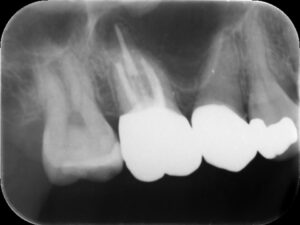

右側上顎第一大臼歯の初診時レントゲン。他院にて根管治療を行っているが良くならず、歯がひびく、黄色い鼻水が続いているとのこと。耳鼻科にて歯性上顎洞炎の診断を受ける。

根管充填後レントゲン。症状が軽快したのでバイオセラミックシーラーとガッタパーチャにて根管充填を行った。根尖までしっかりと薬が入っているのが分かる。

治療後レントゲン。初診時の症状は完全に消失し治癒した。被せ物の適合は根管治療の予後に影響するので、しっかりとフィットする被せ物を装着することが重要。